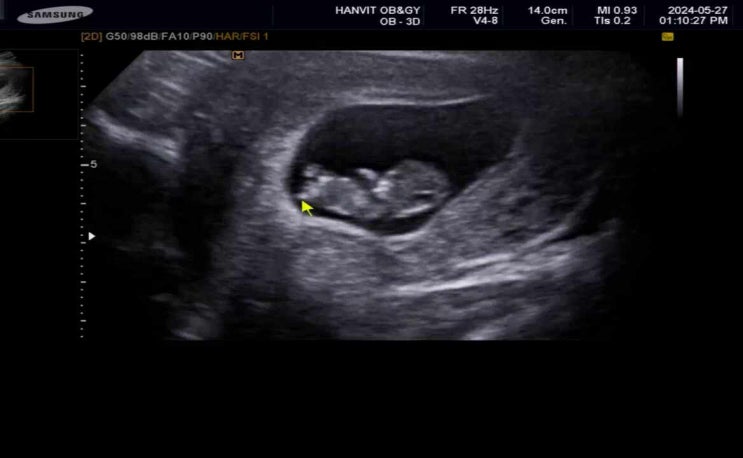

[15주차0일]그새 폭풍성장한 뽀물이(2차신경관결손 검사)

15주차 0일 그새 폭풍성장한 아기 4주만에 찾은 산부인과 (한빛여성병원 5과 진료) 그 사이 니프티 검사결...